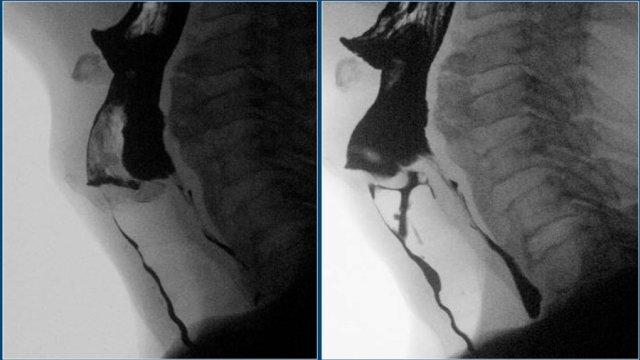

Rối loạn chức năng cơ nhẫn hầu

Mở không đủ và đóng sớm là những vấn đề thường gặp nhất của cơ nhẫn hầu.

Bình thường không nên thấy vết lõm của cơ nhẫn hầu trong quá trình bolus đi qua, nhưng đôi khi thấy một vết lõm nhỏ không gây tắc nghẽn và không có ý nghĩa lâm sàng (Hình).

Tuy nhiên, đôi khi điều này có thể giải thích các triệu chứng của bệnh nhân.

Người ta cho rằng sự đi qua của thức ăn kích thích niêm mạc phủ trên cơ nhẫn hầu, gây ra cảm giác vướng họng (globus sensation).

TRÁI: túi thừa nhỏ. GIỮA và PHẢI: túi thừa Zenker thực sự do đóng sớm của cơ nhẫn hầu (mũi tên vàng)

Túi thừa Zenker

Túi thừa Zenker luôn là hậu quả của rối loạn chức năng cơ nhẫn hầu.

Đóng sớm của cơ nhẫn hầu dẫn đến tăng áp lực trong hạ hầu, ngay phía trên cơ nhẫn hầu, khi sóng áp lực của các cơ khít hầu đẩy bolus xuống dưới.

Áp lực tăng này có thể gây phồng ra tại điểm yếu trên thành hầu sau (khe hở Killian).

Ban đầu sẽ tạo thành một túi nhỏ, theo thời gian có thể phát triển và hình thành túi thừa Zenker thực sự (Hình).